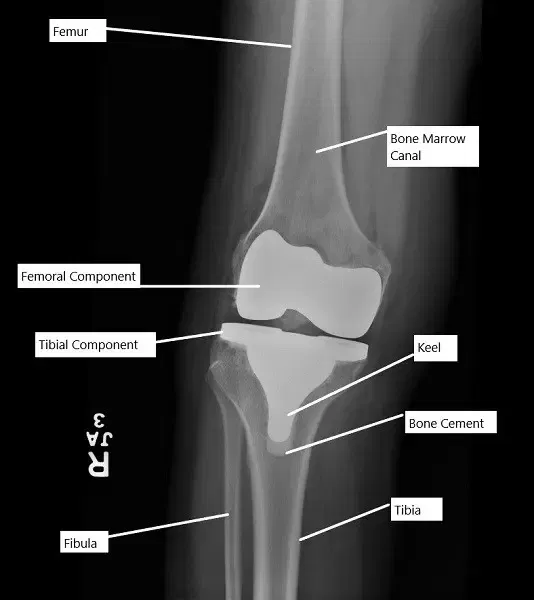

X-ray showing a total knee replacement.

The knee joint is a hinge joint made up of the femur (thigh bone), tibia (shin bone), fibula (calf bone), and patella (kneecap). Ligaments, tendons, and cartilage help stabilize and allow movement in the knee. In total knee replacement surgery, the damaged portions of the femur and tibia are removed and replaced with metal and plastic components to restore the joint’s function.